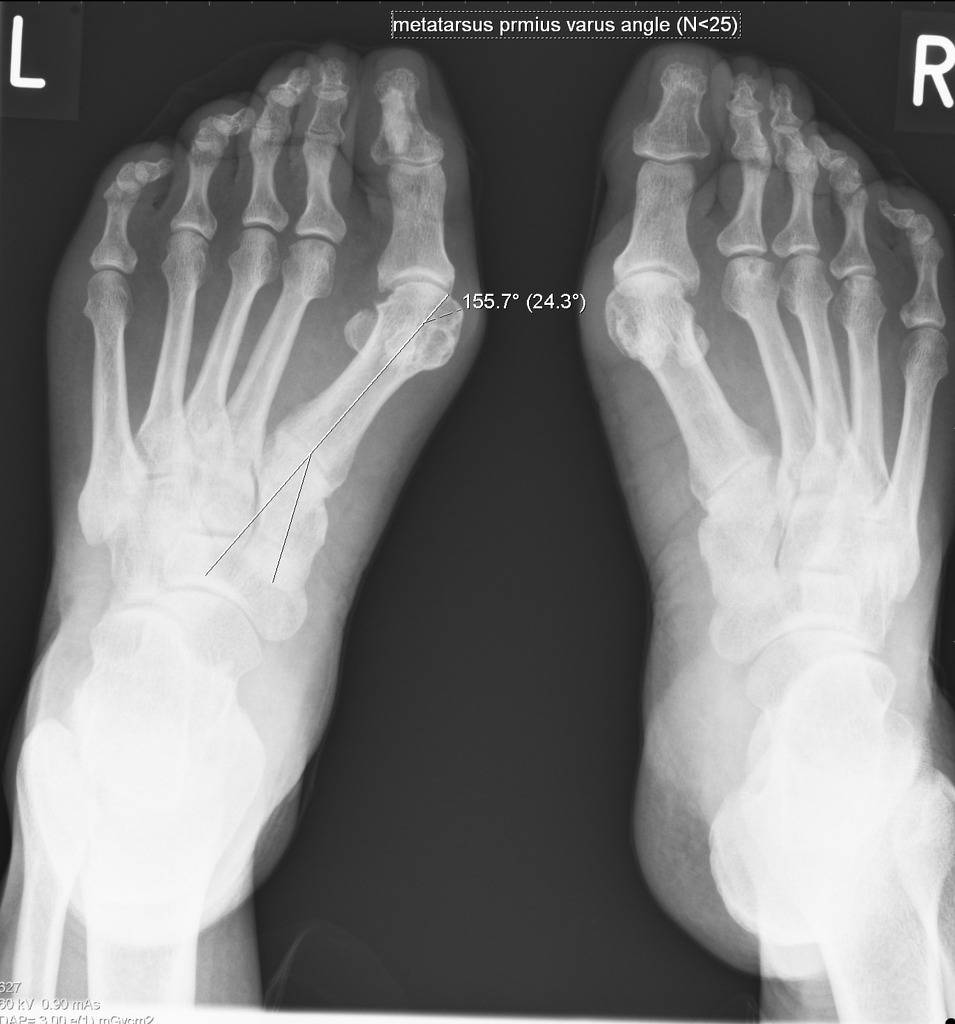

Степени и виды деформации стопы при вальгусной деформации

В зависимости от причин формирования болезненной шишки в области большого пальца, врачи выделяют несколько видов патологии, среди которых: статическая, структурная, травматическая, паралитическая, рахитическая и гиперкоррекционная деформации. Определить это можно только на основе полноценной диагностики стопы.

В зависимости от выраженности симптоматики, врачи выделяют три степени вальгусной деформации стопы:

- Легкая (1 стадия) – пациент жалуется на умеренный дискомфорт в области стопы, а визуально отмечается легкая отечность и покраснение тканей возле большого пальца. При осмотре специалист выявит высоту продольного свода стопы в пределах 15-20 мм, угол наклона пятки до 15 градусов и угол высоты свода до 140 градусов.

- Средняя (2 стадия) – на этой стадии появляется выпирающая косточка на боковой поверхности стопы, а пациент испытывает сильную боль при ходьбе и не может носить обувь без дискомфорта. Со стороны специалистов симптомы средней стадии вальгусной деформации следующие – высота свода до 10 мм, угол наклона пятки до 10 градусов, угол высоты свода 150-160 градусов.

- Тяжелая (3 стадия) – в этом случае пациент испытывает сильную острую боль в области стопы не только во время ходьбы, но и в состоянии покоя. Существенные деформации стопы приводят к нарушению походки, повышению нагрузки на позвоночник и перекосу всего тела пациента. Это приводит к серьезным патологиям позвоночного столба, суставов и костей. Врач при этом отметит следующие характеристики деформации стопы: высота свода 0-5 мм, угол наклона пятки 0-5 градусов, угол высоты свода 160-180 градусов.

Диагностика вальгусной деформации

Основные признаки заболевания врач терапевт, подолог или ортопед определит уже при визуальном осмотре и пальпации пораженной стопы. При внешнем осмотре специалист отмечает, что больной опирается на пол не наружным краем стопы, а всей поверхностью. Продольная ось стопы искривлена, а пятка отклонена наружу.

При сведении ног в положении стоя, пациент не может соединить пятки. На поздних стадиях развития заболевания уже заметна выпирающая косточка большого пальца, отмечается отечность и покраснение в области сустава.

Для подтверждения диагноза назначается аппаратная диагностика — плантография, рентгенография стоп и подометрия. На рентгеновских снимках при развитии вальгусной деформации отмечается уменьшение высоты свода стопы, а также нарушение взаиморасположения переднего, среднего и заднего отделов стопы.

Подометрия позволяет выявить неравномерное распределение нагрузки со смещением в область носовой части стопы. Чтобы определить причины развития патологии пациенту дополнительно могут назначить консультацию следующих врачей: невролога, нейрохирурга, эндокринолога, гинеколога.